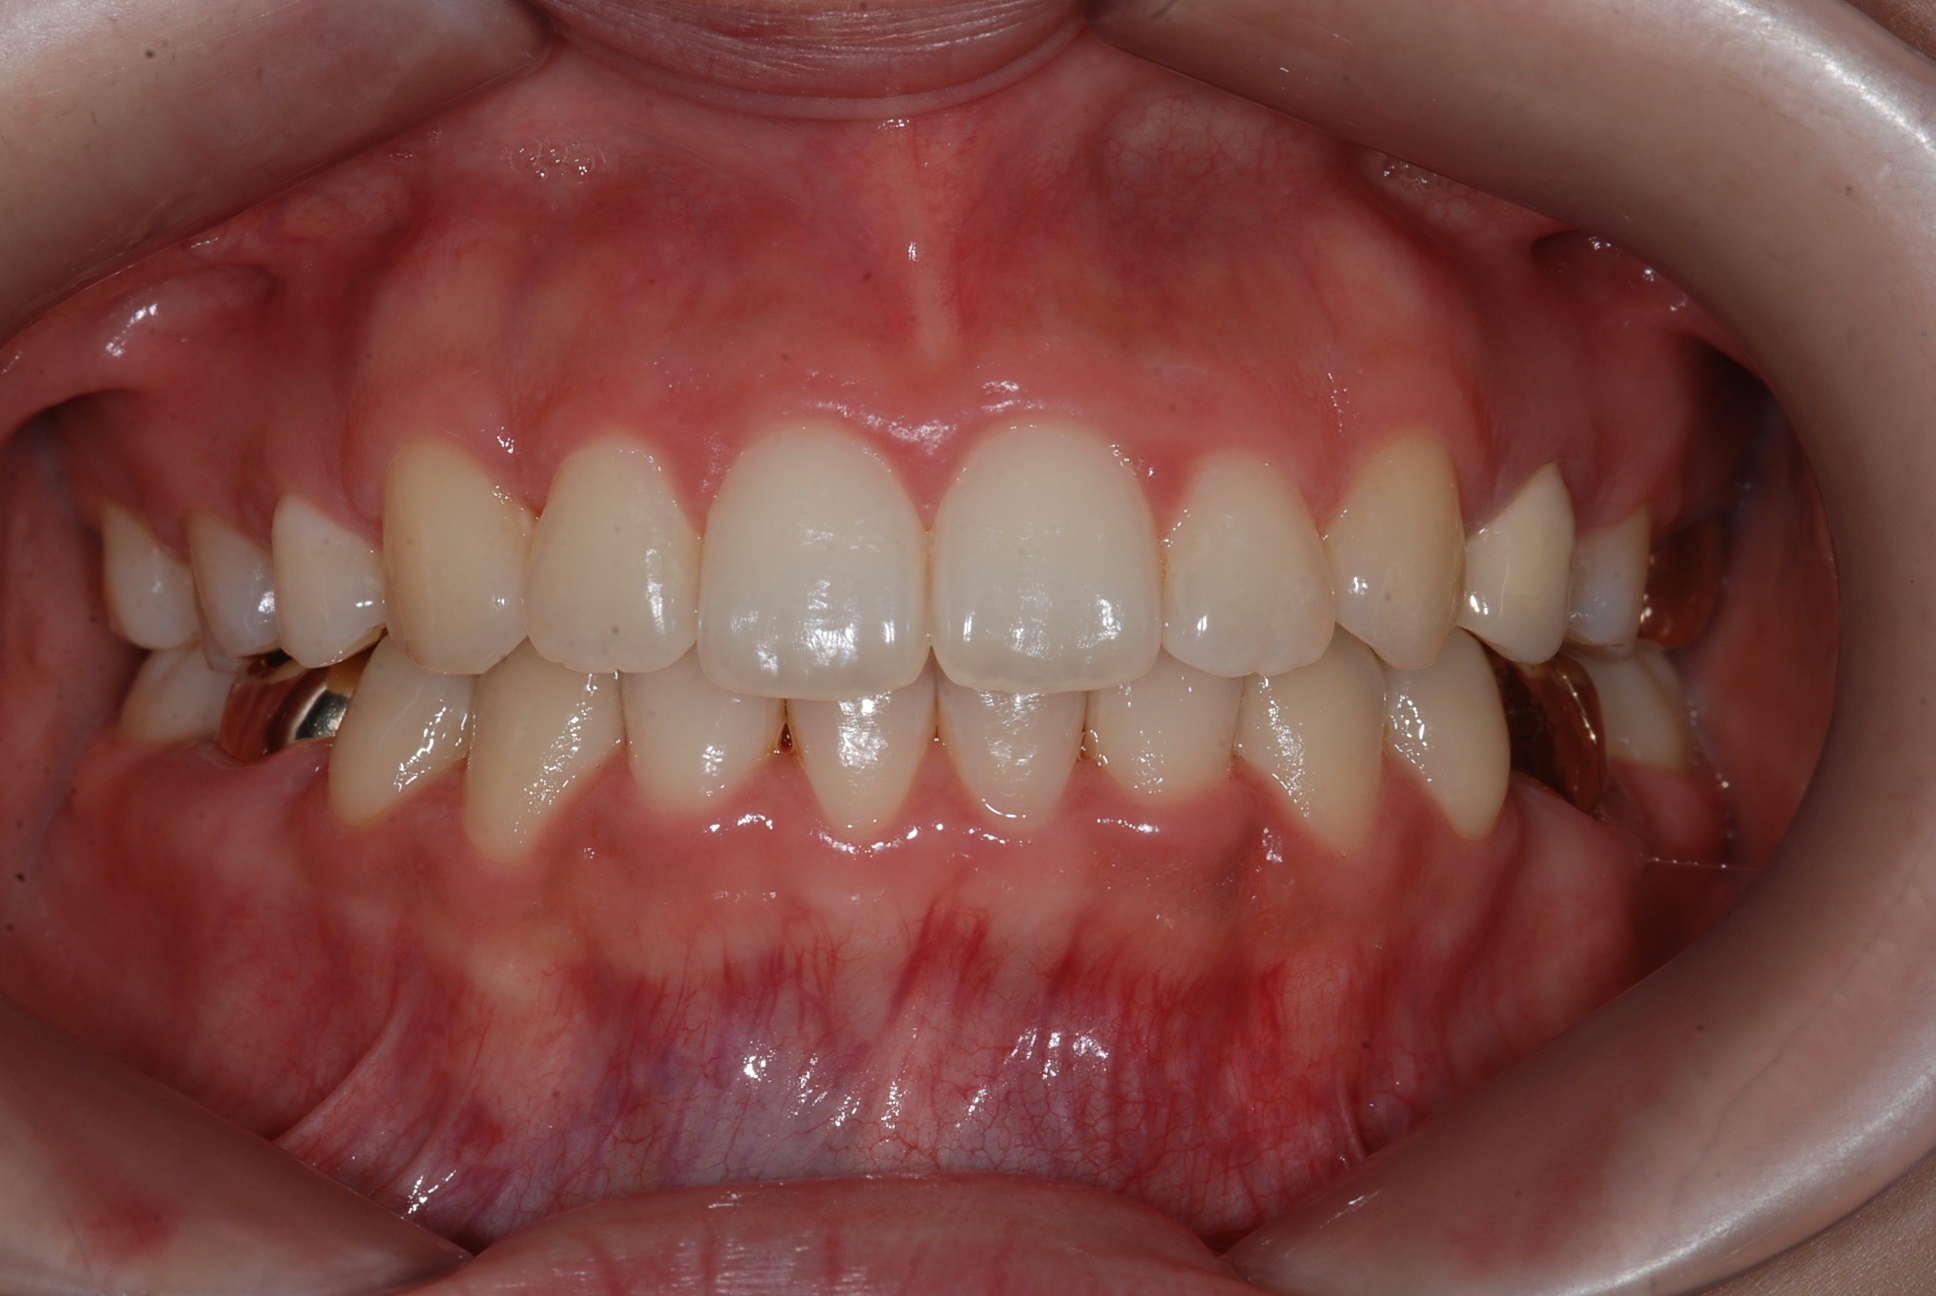

치료 후 사진입니다.